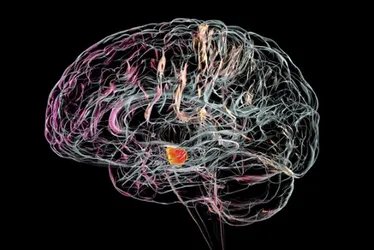

Cientistas australianos desenvolveram uma terapia celular para o tratamento do Parkinson que dispensa drogas imunossupressoras e restaura a função muscular. A abordagem, testada em camundongos, é vista como um avanço científico promissor e apontada como a próxima geração em tratamentos neurológicos.

Os pesquisadores do Instituto Florey de Neurociência e Saúde Mental em Melbourne, Austrália, criaram uma maneira de enganar o sistema imunológico, fazendo-o aceitar enxertos de neurônios modificados como parte do corpo, em vez de atacá-los como objetos estranhos.

Ao contrário dos medicamentos atuais, que tratam os sintomas da doença, os enxertos de neurônios modificados têm como alvo a causa, substituindo neurônios mortos. O avanço foi publicado na quarta-feira (10/4), na revista Cell Stem Cell.